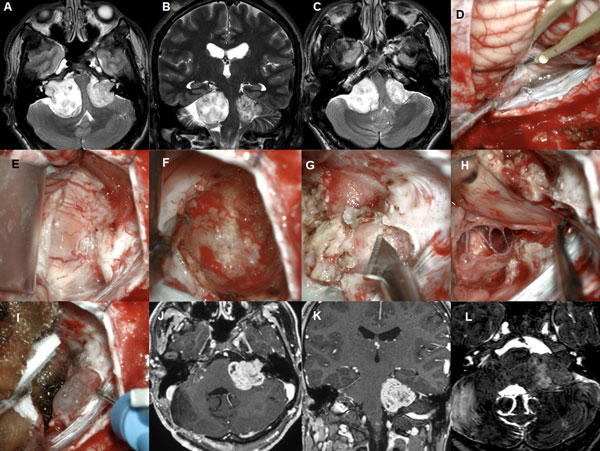

Figura 5: Paciente masculino de 18 años, operado de SV T4b bilateral. A-C: RM cerebral preoperatoria. D-I: imágenes intraoperatorias (lado derecho), D-F descompresión intratumoral con aspirador ultrasónico, G-H descompresión del complejo VII-VIII, I: oclusión del CAI con cola de fibrina., J-L: RM cerebral postoperatoria

Figura 6: Paciente femenino de 72 años, operado de SV T3b con quiste externo. A-C RM preoperatoria, D-I: imágenes intraoperatorias, D-F descompresión intratumoral con aspirador ultrasónico, G-H descompresión del complejo VII-VIII, J-L: RM cerebral postoperatoria.